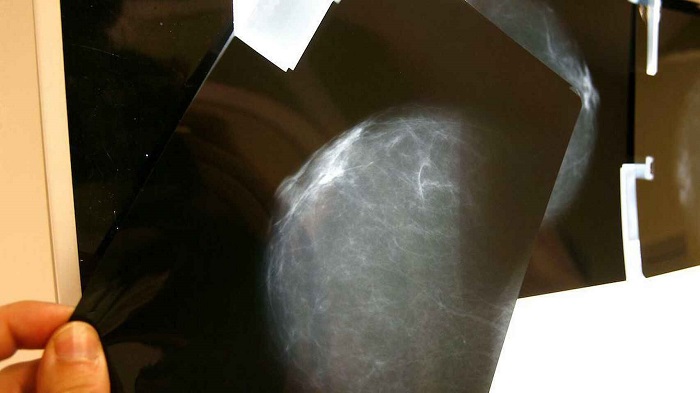

"Aunque las mamografías son una herramienta útil para detectar el cáncer de mama de forma precoz, no se suelen recomendar a las mujeres de bajo riesgo menores de 40 años --explica Danielle Whitham, candidata al doctorado en la Universidad Clarkson de Nueva York (Estados Unidos)--. Dado que los biomarcadores que hemos encontrado en la leche materna son también detectables en el suero sanguíneo, el cribado podría realizarse potencialmente en mujeres de cualquier edad utilizando sangre o leche materna".

Los biomarcadores recién identificados corresponden a un tipo específico de cáncer denominado carcinoma ductal invasivo (CDI), uno de los tipos más comunes de cáncer de mama. Sin embargo, los investigadores afirman que su método podría utilizarse para identificar biomarcadores para otros tipos de cáncer de mama.

Los biomarcadores recién identificados corresponden a un tipo específico de cáncer denominado carcinoma ductal invasivo (CDI), uno de los tipos más comunes de cáncer de mama. Foto: Andrés Cristaldo, EFE